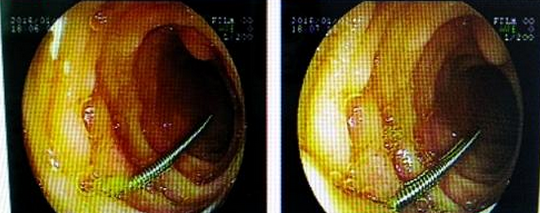

2日下午5时,手术正式开始,麻醉师首先对患儿实施了全麻。由消化内科医生采用胃镜检查治疗。这个手术的难度非常大,小儿胃镜的直径是0.9CM,患儿还不到一岁,在如此狭窄的消化道内进行操作是非常危险的。手术中从显示屏可以清楚地看到,随着胃镜小心地推进食道、胃,均未发现钢针,当胃镜到达十二指肠降部时,发现吞下的钢针正卡在这里,钢针一半已插入肠壁中。这就意味着:稍有操作不慎,针尖或许会划破肠襞及周围的脏器,引起肠穿孔或脏器大出血。

如果由外科医生手术直接取异物,给孩子造成的损伤和风险也是很大的,当时在手术室参加抢救的医生们一致认为,尽最大的可能采用胃镜取出异物。消化科医生操作胃镜试图将钢针夹住、小心退出插入的肠壁。经过将近三个小时的不断努力,最终一点一点地将这个钢针从孩子的肠道拖了出来。